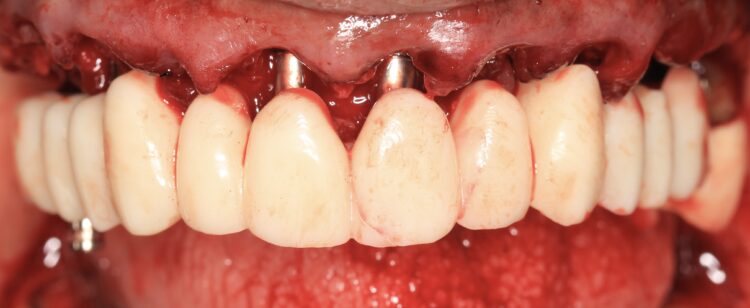

The plan was followed meticulously on the day of surgery. The canines, left and right premolars and a right molar were used to support the surgical guide together with three bone anchor pins. Following the digital plan, all other teeth were extracted and thorough degranulation of the sockets was performed. No bone reduction was performed for both the provisional and final prosthesis in accordance with the Misch classification for an FP1 approach.[iv]

The implant beds were then prepared with the surgical guide in situ. Six CONELOG® Progressive-Line implants from BioHorizons Camlog were placed in accordance with the predetermined positions, depths and angulations. These implants were selected for this case because they feature an optimal thread design and tapered figure, promoting high primary stability – which is essential in full arch reconstruction cases.

The implants were placed through the guide for better accuracy and precision. A surgical primary stability of >35Ncm was achieved for each implant. Once the implants were placed, the surgical guide was removed, and the extraction of the remaining teeth was completed.